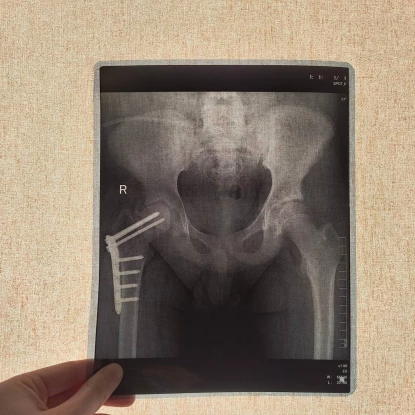

У Львові вперше в Україні підлітку зростили стегнову кістку стовбуровими клітинами. Фото: Дитяча лікарня Святого МиколаяУ Львові лікарі вперше в Україні зростили стегнову кістку 14-річному підлітку за допомогою технології введення стовбурових клітин.

У червні 2025 року у підлітка виникла нова проблема — він не зміг підвестися з ліжка. Спочатку лікарі підозрювали параліч або поліомієліт, однак обстеження показало перелом шийки стегна.

Як з’ясувалося, кістка зламалася без травми через крихкість. Аналізи показали критично високий рівень креатиніну — близько 700, що свідчило про тяжке ураження нирок і порушення мінерального обміну.

У лікарні Дніпра підлітку зафіксували перелом гвинтами. Після цього стан нирок різко погіршився, і вони повністю відмовили. Відтоді хлопець перебуває на гемодіалізі. Через слабкість кісткової тканини гвинти змістилися та почали руйнувати кульшовий суглоб.

У Львові вперше в Україні підлітку зростили стегнову кістку стовбуровими клітинами. Фото: Дитяча лікарня Святого МиколаяЗ огляду на необхідність трансплантації нирки родина звернулася до лікарів Першого медоб’єднання Львова. У Дитячій лікарні Святого Миколая пацієнта також оглянули ортопеди-травматологи та вирішили застосувати сучасну методику відновлення кістки за допомогою стовбурових клітин.

Лікарі ввели стовбурові клітини безпосередньо в місце перелому. Їх отримали з жирової тканини пацієнта. За словами медиків, ця методика стимулює утворення нових кісткових клітин і сприяє зрощенню.

У лікарні зазначають, що ця технологія є інноваційною та наразі застосовується в Україні лише в цьому медзакладі.

Після процедури минуло два тижні. Підліток уже почав ставати на ногу з опорою на ходунці. Лікарі очікують, що після повного зрощення кістки він зможе самостійно ходити.